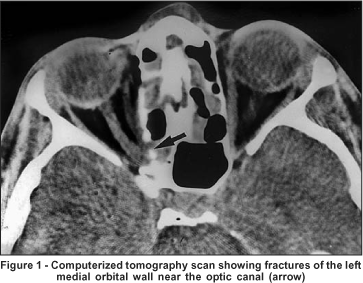

A computerized tomography scan revealed multiple fractures of the left medial orbital wall, including one near the optic canal (Figure 1). Treatment with high doses of intravenous corticosteroids was initiated and two days later an optic canal decompression was performed through frontal craniotomy. During surgery, when viewed from above the optic nerve appeared normal and without any evidence of hematoma. However, a direct visualization of the inferior and nasal aspects of the nerve was not possible. Vision did not improve after surgery and total optic nerve atrophy developed two months later in OS.